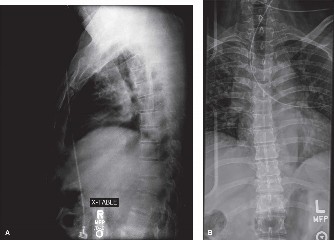

The diagnostic imaging workup for this patient spanned his initial presentation at age 15 and his subsequent return at age 20, providing a textbook illustration of the natural history of untreated isthmic spondylolysis. During his initial visit, standard weight-bearing anteroposterior (AP), lateral, and bilateral oblique radiographs of the lumbar spine were obtained. The lateral radiograph demonstrated a normal lumbar lordosis and preserved L5-S1 disc space height, with no evidence of anterior translation (spondylolisthesis). However, the oblique radiographs revealed the pathognomonic "collar on the Scotty dog" sign. The "Scotty dog" represents the posterior elements of the vertebra, where the nose is the transverse process, the eye is the pedicle, the front leg is the inferior articular process, and the neck is the pars interarticularis. A radiolucent line across the neck confirmed the presence of bilateral L5 pars defects.

Upon his return five years later, the imaging profile was drastically different. Standing lateral radiographs now revealed a Meyerding Grade 2 spondylolisthesis at L5-S1, indicating that the L5 vertebral body had translated anteriorly by 25% to 50% over the sacral promontory. Furthermore, there was a noticeable collapse of the L5-S1 intervertebral disc space, signifying advanced degenerative changes secondary to the altered biomechanics and chronic instability. We also meticulously measured the patient's spinopelvic parameters on a standing 36-inch scoliosis cassette. His Pelvic Incidence (PI) was measured at 65 degrees (high), which mathematically dictates a higher Sacral Slope (SS) and Pelvic Tilt (PT). A high PI is a known biomechanical risk factor for the progression of spondylolisthesis, as it creates a steeper lumbosacral shear angle, placing immense anterior translational force across the compromised L5-S1 segment.

Clinical & Radiographic Imaging Archive